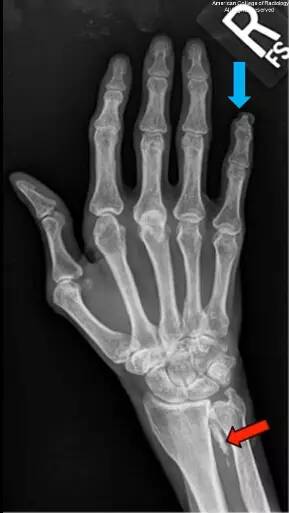

图 3 为右手后前位,可见小指肢端骨质溶解(蓝色箭头)。仍可见软组织钙化灶(红色箭头)。肌萎缩明显